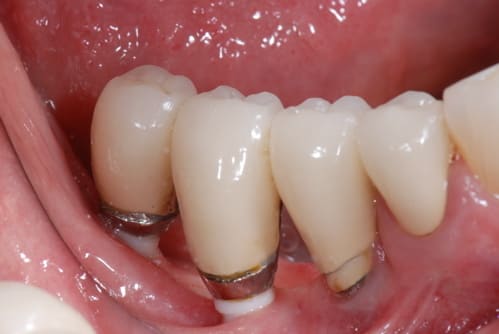

pour le débat, voici ce que j'ai posé en 1990, 1 TBR vissé + 2 zircones vissés de Sandhaus, et voici le résultat 17 ans plus tard. comme le mélange des genres va interpeller, j'explique. il s'agit là de la 2ème pose d'implant de ma carrière débutante, alors que je faisais le DU de la Salpétrière. c'était à l'époque où l'on débatait sur le risque de solidariser un implant à une dent. j'ai finalement préféré ne pas solidariser mes 2 implants 36-37 à la 34 et j'ai donc rajouté un implant en 35 par la suite; entre temps, j'avais abandonné les implants en zircone car la technique chirurgicale proposée avec ne me plaisait pas et que celle proposée pour les implants en titane me convenait davantage. il s'agissait déjà pour Sandhaus de poser les implants sans faire de lambeau et pour le débutant que j'étais, je trouvais ça trop délicat; j'ai donc terminé le cas avec un TBR en technique Branemark plus sécurisante.